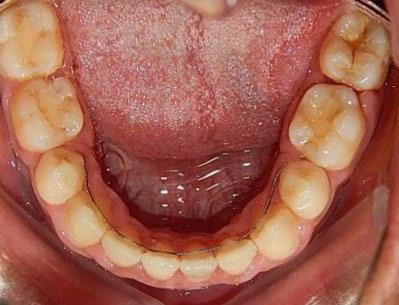

En los estudios intraorales, las fotografías iniciales muestran clase I canina y molar bilateral, mordida anterior abierta, apiñamiento leve superior e inferior, y líneas medias dentales

desviadas. En las Figuras 4, 5 y 6 se observa la forma de las arcadas superior e inferior.

Figura 6. Oclusal superior e inferior de inicio.